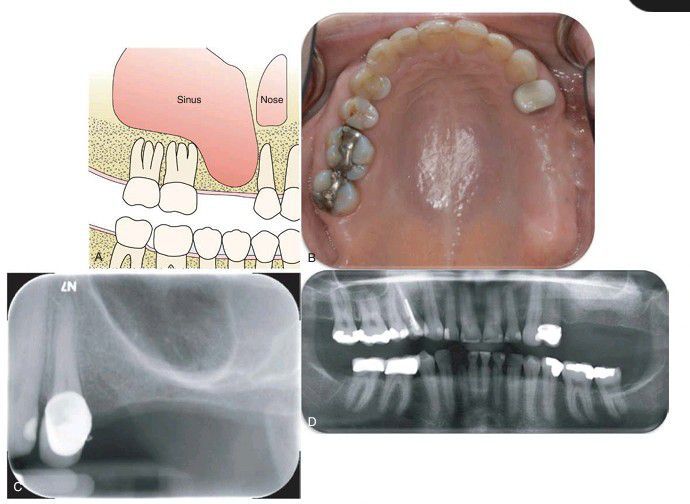

. (A) Diagram illustrating pneumatization of the maxillary sinus into the alveolar ridge with inadequate bone support for reconstruction. (B) Pretreatment image of a patient missing teeth #13 and #14. (C) Pneumatization of the maxillary right sinus. (D) Postoperative Panorex showing left maxillary sinus lift using a combination of particulate allogenic and xenograft via a lateral window approach.